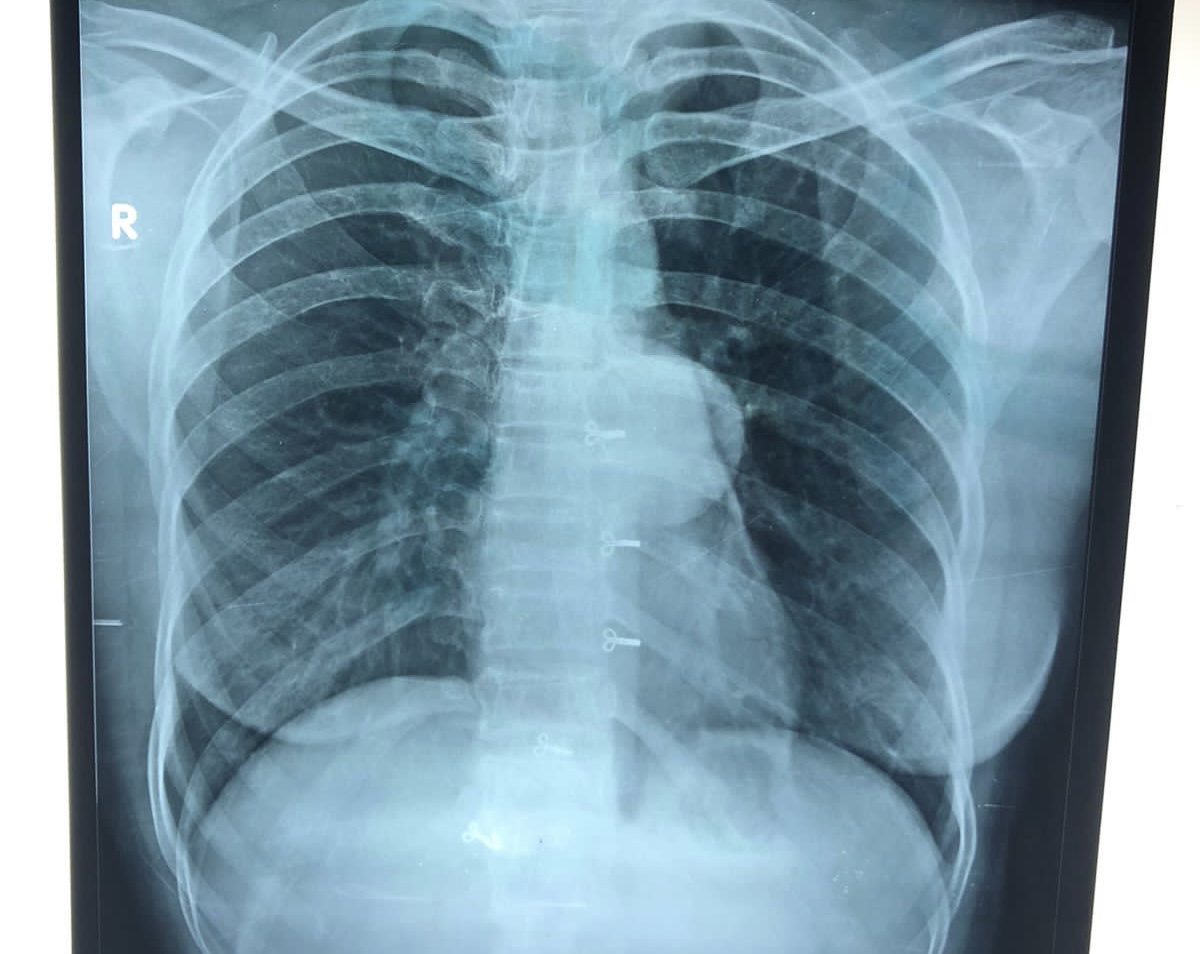

29 year old female came for surgical checkup with xray

XRAY:

Left margin of the heart is clearly seen through the lesion

-Posterior mediastinal massMri: